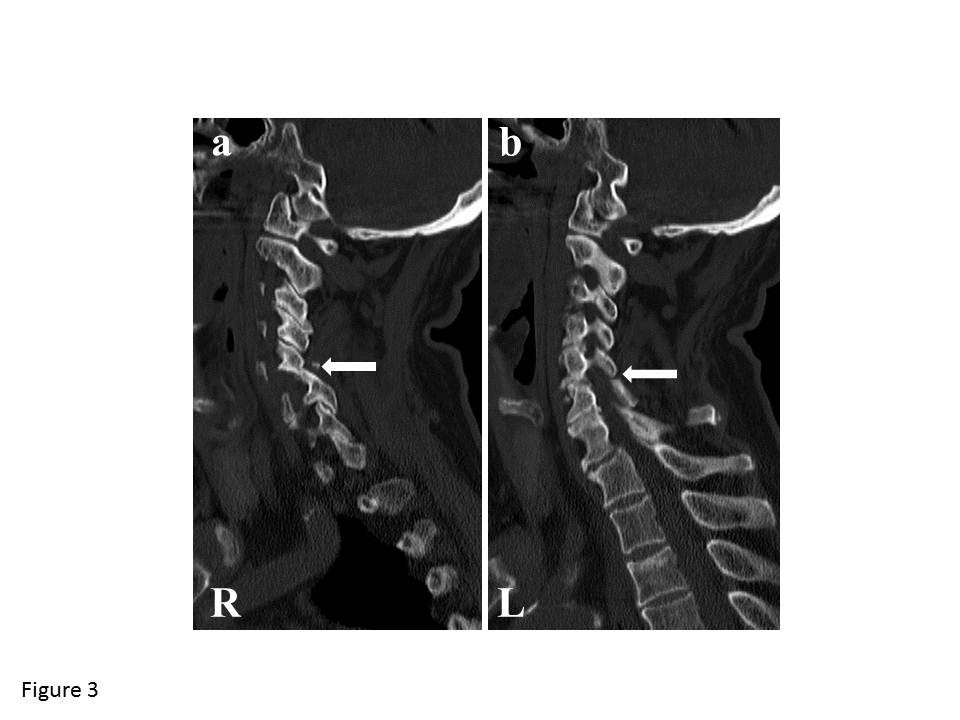

From www.researchgate.net

Case 4 Preoperative CT showing C5C6 facet fracture dislocation and Facet Joint Dislocation 10% of cervical spine injuries. learn about the causes and signs of facet joint pain, a common condition that affects the lower back. the “reversed hamburger”, “naked facet” and “headphones” signs represent cervical facet joint dislocations. Find out how doctors diagnose and treat facet joint. Facet joint dislocations secondary to flexion distraction injury. traumatic dislocations of facet. Facet Joint Dislocation.